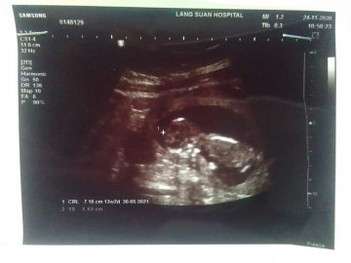

เเม่ๆบ้านไหนเป็นเหมือนกันไม่ค่ะ กลางคืนนอนไม่หลับเลยปวดเมื่อยไปทั้งตัวเลยค่ะ #14w2daysท้องเเรกค่ะ #ขอคำแนะนำหน่อยค่ะ